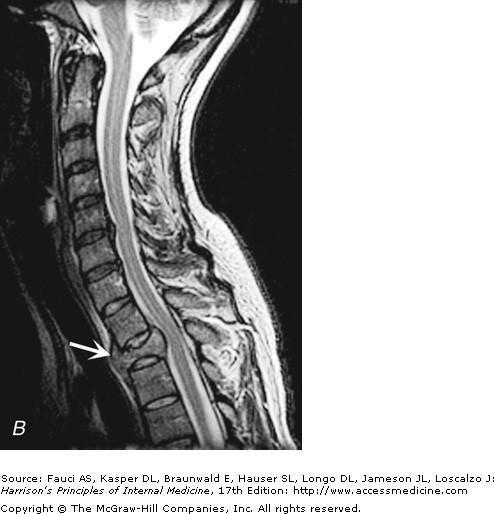

Metastatic breast ca with epidural compression